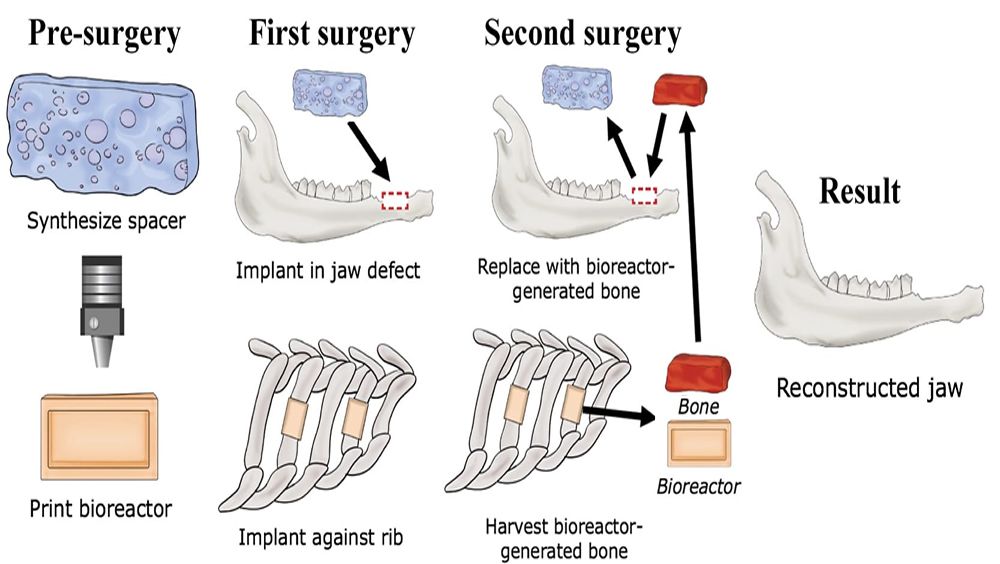

Para avanzar en este proceso, investigadores de la Universidad de Rice han desarrollado una técnica para cultivar huesos vivos con el objetivo de reparar lesiones mediante la colocación de un biorreactor impreso (un molde) en 3D. Y es que, este está hecho para ser unido a los huesos de las costillas y, una vez implantado, poder soportar las células madre y la formación de vasculatura sanguínea. El molde se puede hacer a la medida de las necesidades del paciente y, después de algunos meses de crecimiento, el biorreactor se puede explantar y el hueso se puede trasplantar a otra parte del cuerpo.

No obstante, esta técnica está especialmente indicada para la cirugía craneofacial y neurocirugía, donde los huesos pequeños son de un uso muy necesario.

Así, este nuevo método se está desarrollando para reemplazar las técnicas de reconstrucción actuales que utilizan tejidos de injerto óseo extraídos de diferentes áreas de un paciente, como la parte inferior de la pierna, la cadera y el hombro.

''Una innovación importante de este trabajo es aprovechar un biorreactor impreso en 3D para formar hueso crecido en otra parte del cuerpo, mientras que preparamos el defecto para aceptar el tejido recién generado'', ha señalado Antionios Mikos, profesor de Bioingeniería en la Universidad Rice.

Por su parte, Mark Wong, uno de los investigadores de esta técnica, ha señalado que ''los estudios anteriores establecieron una técnica para crear injertos óseos con o sin su propio suministro de sangre a partir de hueso real implantado en la cavidad torácica. Este estudio ha demostrado que podemos crear injertos óseos viables a partir de materiales sustitutos de huesos artificiales''.

Ha añadido, a su vez, que ''la ventaja significativa de este enfoque es que no es necesario extraer el propio hueso de un paciente para hacer un injerto óseo, sino que se pueden usar otras fuentes no autógenas''.